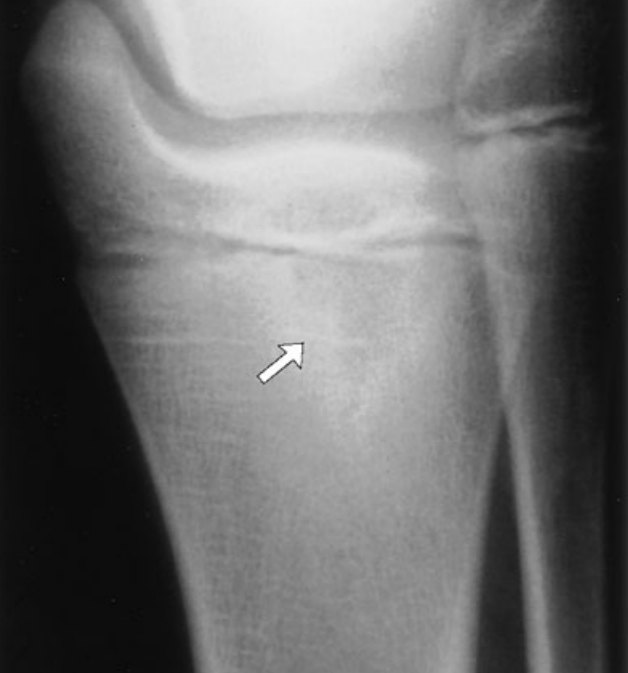

Osteomyelitis

cause: Although usually the result of hematogenous bacterial spread, particularly of S aureus, can follow an episode of deep cellulitis or septic joint and should be suspected whenever these occur.,

symptoms: Acute osteomyelitis tends to begin abruptly, with fever and marked, localized bone tenderness that usually occurs at the metaphysis. Redness and swelling frequently follow.

diagnosis: clinical, xray shows lytic lesions. Bone scans with radionuclides, however, can be useful in the diagnosis of osteomyelitis within 24 to 48 hours of symptoms and in its differentiation from cellulitis and septic arthritis. Magnetic resonance imagining (MRI) has become more widely used for the diagnosis of osteomyelitis, as it is very sensitive and specific.